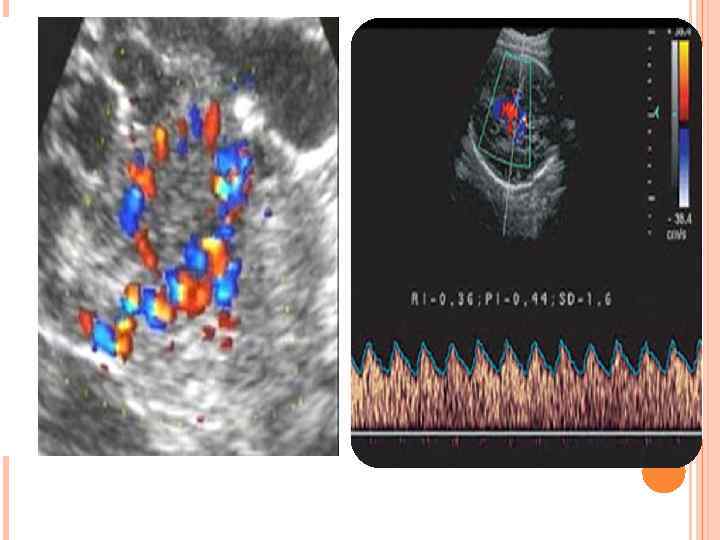

Допплерография аппаратын 1842 жылы Австрияның физигі және астрономы Доплер ашты. Допплер – толқын тербелісінің жиілігінің қозғалыс кезінде өзгеруі. Клиникалық және лабораториялық практикада допплерографияны гемодинамика тамыр пульсациясын , тамырдағы тромбтар мен эмболияны, көп ұрықты жүктілікті, плацентаның орналасу орнын, құрсақтағы шарананың жүрегінің жұмысын анықтауда кеңінен қолданылады.

Ультрадыбыстық допплерография • • • 16 МГц импульсттік режим сканирлеудің жету мөлшері 5 -20 мм